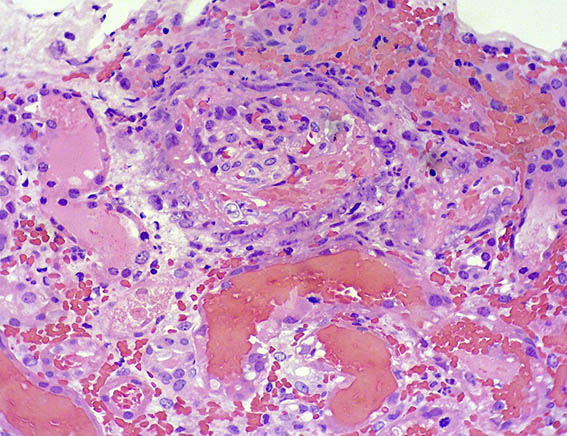

Figure 1.

H&E, X100.